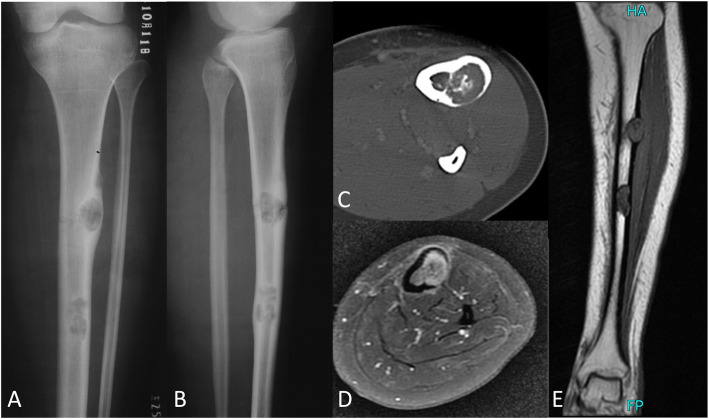

OFD-like and classic AD showed similar imaging characteristics (Figs. 1 and 2). The tumor was located in the cortex of the tibia or fibula, which showed expansile lytic lesions with varying degrees of osteolysis and osteosclerosis. CT showed cortical destruction, with cysts separated by sclerotic bony septa. MRI revealed different tumor foci with high signal intensities on T2-weighted images and T1-weighted contrast-enhanced images. Imaging showed whether the lesions were fibro-osseous, but neither CT nor MRI was able to differentiate between OFD-like and classic AD.

Fig. 2.

Representative images of classic adamantinoma. Radiographs showing a anterior-posterior and b lateral views of two lesions in the tibial shaft. c CT image showing the extent of the tumor in the cortex. d, e MR images showing the extent of the tumor